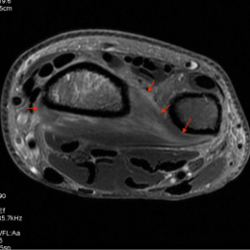

Le Muscle Carré pronateur (Musculus Pronator Quadratus) forme à lui seul, la couche musculaire profonde de la face antérieure du poignet

Aplati et quadrangulaire, il est tendu transversalement entre la partie inférieure des 2 os de l'avant-bras. Sa hauteur est de 6 cm, sa largeur de 3 à 4 cm.

- on peut le décomposer en 2 plans : superficiel et profond